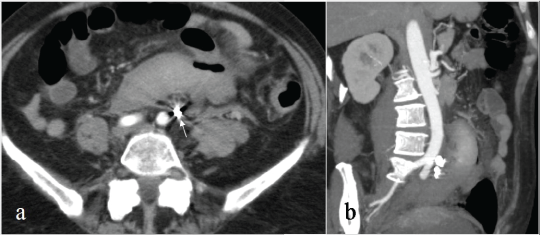

The follow-up was performed by a clinical examination and a CTA 1 week after the procedure and after 3 months (Figure 3a and Figure 3b).

Figure 3a-b: Axial image (a) and MIP reconstruction (b) of a CT scan performed 1 week later, demonstrating the complete exclusion of the aneurysm with artifacts due to the metallic coils (arrow); the retroperitoneal hematoma was almost unchanged.